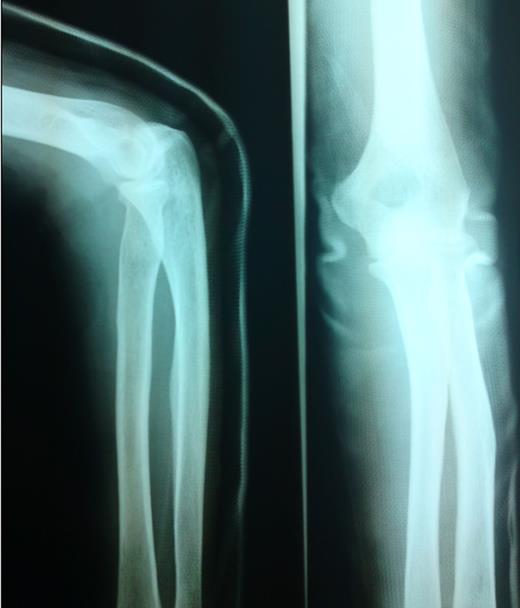

Posterior splint was applied in ED and X-rays showed no fracture, no dislocation.